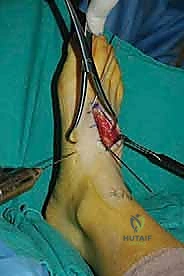

إعادة بناء رباط الكاحل الجانبي المزمن بالطعوم الذاتية: خبرة الأستاذ الدكتور محمد هطيف في صنعاء

استعادة ثبات الكاحل ووظيفته بمعالجة عدم استقراره المزمن عبر إعادة بناء الرباط الجانبي باستخدام الطعم الذاتي (وتر الرشيق). تعرف على التقنية …